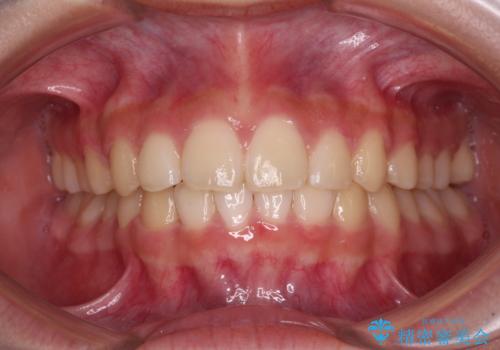

ワイヤー装置と補助装置を有効に活用し、さらには高校生ということもあり、1年9か月で狙い通りの仕上がりを達成することができました。

下の前歯が隠れてしまうほど深い咬み合わせ 高校生のインビザライン矯正治療